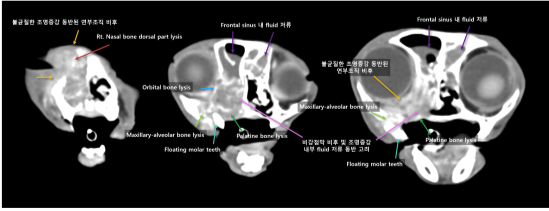

고양이 구강 SCC 방사선 치료용 모의 CT 촬영 / 출처: 에스동물암센터

고양이 구강 SCC 방사선치료 후 CT 촬영 결과 1 / 출처: 에스동물암센터

고양이 구강 SCC 방사선치료 후 CT 촬영 결과 2 / 출처: 에스동물암센터

📌방사선 치료 1달 후 결과

기존에 코안에 크게 자리 잡고 있던 종양 덩어리가 눈 주위 뼈, 코뼈 등 광범위하게 퍼져있었습니다. 방사선 치료 1개월 차 CT 촬영 결과, 종양 크기는 줄어 현재 코 안쪽에 1.3cm 정도의 종양만 남이 있는 것으로 확인되었습니다.

다만, 코 안과 부비동에는 여전히 분비물/액체가 차 있는 모습이 보여, 염증(비부비동염)이 남아있을 가능성이 있어 이후 리첵 평가가 추천되었습니다.